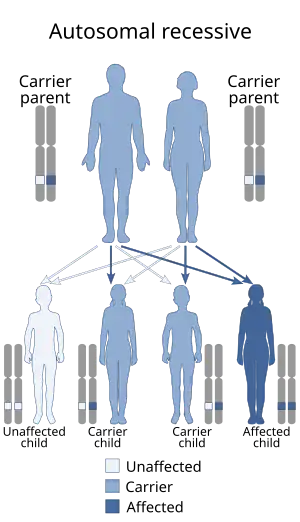

| Autosomal recessive multiple epiphyseal dysplasia has an autosomal recessive pattern of inheritance. | |

The disorder is inherited in an autosomal recessive manner.[2] This means the defective gene responsible for the disorder is located on an autosome (chromosome 5 is an autosome), and two copies of the defective gene (one inherited from each parent) are required in order to be born with the disorder. The parents of an individual with an autosomal recessive disorder both carry one copy of the defective gene, but usually do not experience any signs or symptoms of the disorder.